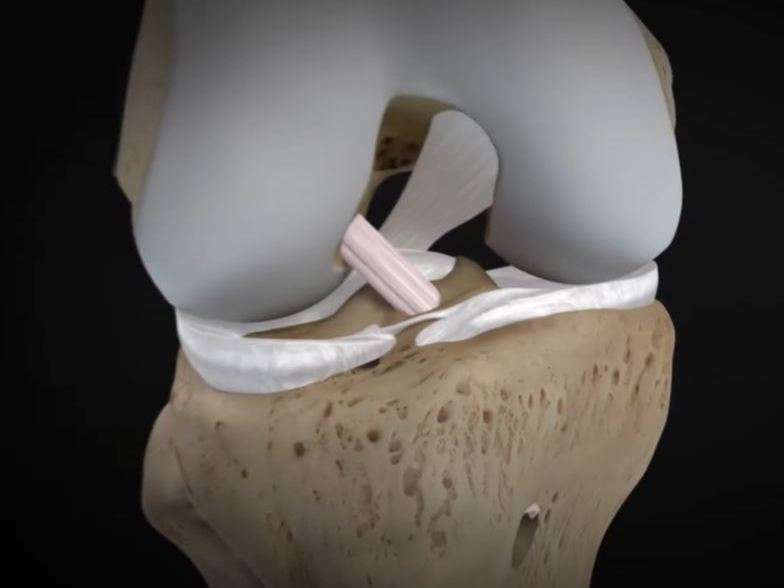

Les ligaments croisés sur des tissus fibro-élastique très solides, insérés entre le tibia et le fémur à l’intérieur de l’articulation du genou dans l’échancrure inter-condylienne. On en compte deux, un antérieur et un postérieur et forme ce que l’on appelle le pivot central.

Le ligament croisé antérieur (LCA) s’insère à la partie antéro-interne du tibia et sur la face interne du condyle fémoral externe. Le ligament croisé postérieur (LCP) est tendu entre la partie postéro-externe du tibia et sur la face externe du condyle fémoral interne.

Ils jouent un rôle de stabilisateur du genou dans les mouvements de torsion et de translation (ou tiroir) antérieur et postérieur.